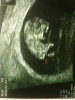

Voila mon bibou

Oh!! C'est trop beau.

3 cm et déjà on voit tellement de chose.

Tu dois effectivement être rassurée de l'avoir vu!